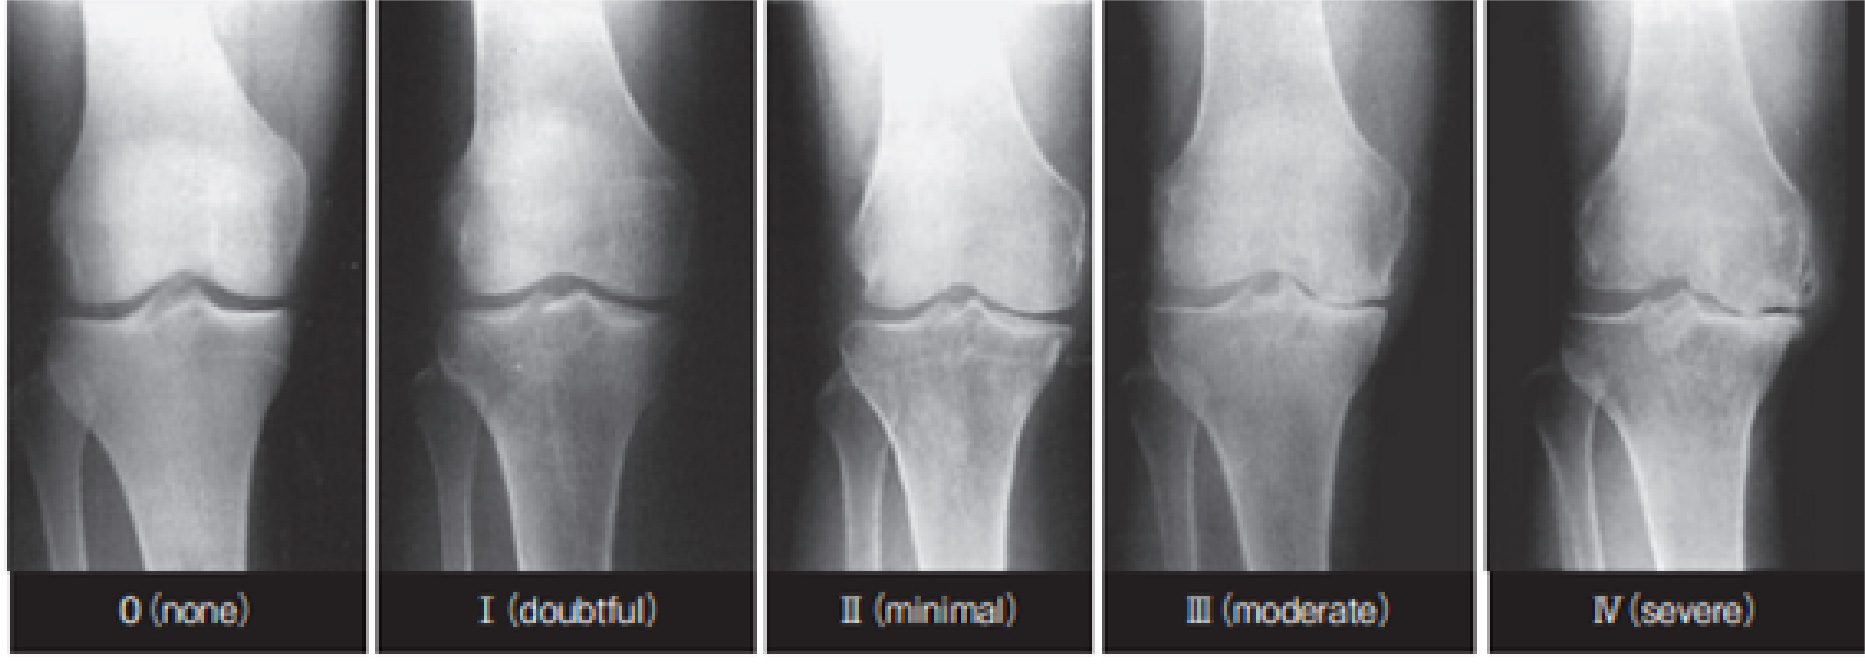

- レントゲン検査(X線)

- 骨や関節の変形の程度を確認し、変形性関節症の進行度を K-L分類 を用いて評価します。

(K-L分類:X線画像より変形性膝関節症の重症度を判定する方法です)